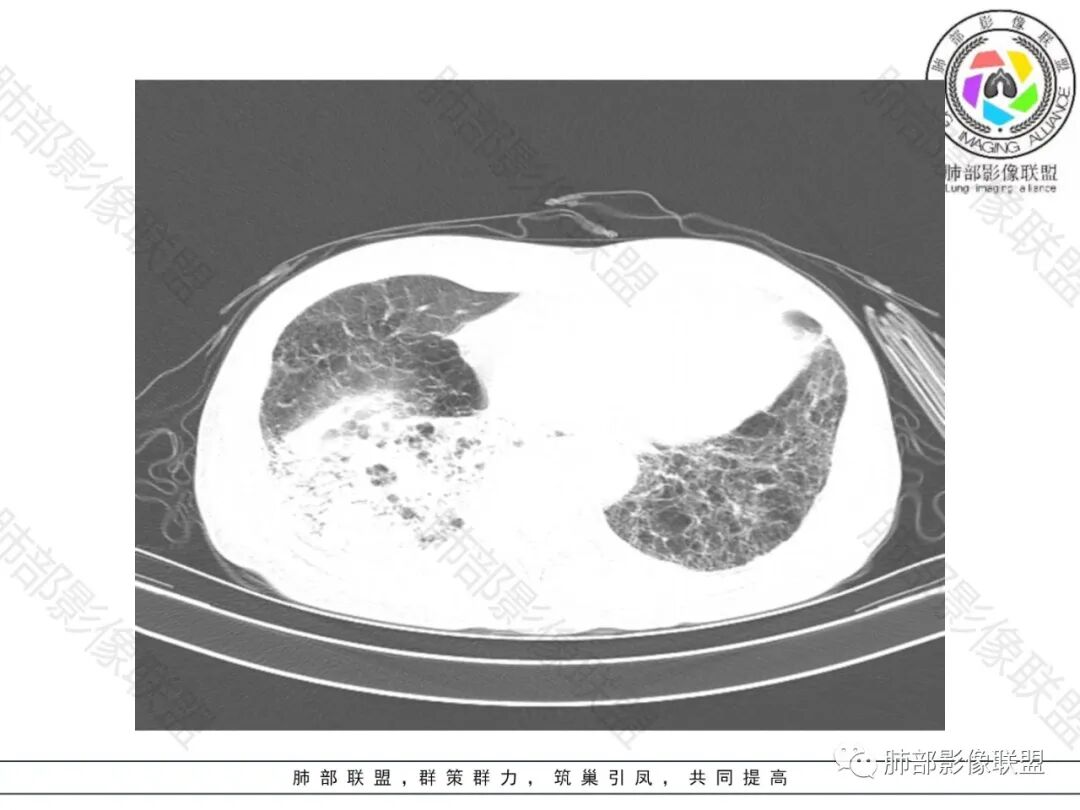

2.影像表现:肺气肿背景,右肺下叶呈现明显网格影及蜂窝影、枯枝征,边缘膨隆、叶间裂向前方推移。病灶密度不均,前份见不规则片状实性密度区,实性部分轻度强化,边界不清,周边特征掩盖不清。支气管主要分支显示,呈枯枝征。纵隔窗病灶密度偏低,病灶内血管影边缘稍显模糊,未见明显液化坏死区。

余双肺未见明显结节影。

右侧肺门淋巴结肿大,中央低密度;纵隔见轻度增大淋巴结。

3.综合分析:临床方面:慢性病程、急性发作,呼吸道症状伴发热,炎性指标升高,提示存在感染可能;CA199升高,但相对特异性不高。影像双肺气肿,右肺下叶蜂窝状改变明显,夹杂实变密度区,支气管相关但未见阻塞,较常见于感染性病变,如G-杆菌感染等。蜂窝影什么时候出现我们不得而知,实变区周边特征掩盖不清。

前后三月余病灶变化不明显,右肺门异常肿大淋巴结让人警惕恶性病变可能性。

因为有肺气肿背景、有蜂窝,周边特征及张力等都不能作为判断依据或参考。单肺叶蜂窝影伴实性密度区被确诊为肺腺癌的例子已不少见,敬请留意。